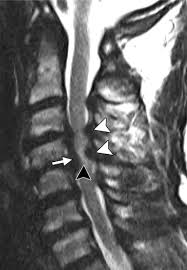

Guillain Barre Syndrome Mri / Figure 6 From Spinal Mri Findings Of Guillain Barre Syndrome Semantic Scholar - Typically, both sides of the body are involved, and the initial symptoms are changes in sensation or pain often in the back along with muscle weakness, beginning in the feet and hands, often spreading to the arms and upper body.. However, it can reveal nerve root enhancement and may be an effective diagnostic adjunct. Moreover, gbs is also associated with any vaccination. Its signs and symptoms are similar to those of other neurological disorders and may vary from person to person. Cerebral magnetic resonance imaging showed lesions in both frontal and right occipital lobes. Fisher syndrome, a clinical variant of guillain­ barre syndrome characterized by ataxia, are­ flexia, and ophthalmoplegia, brain stem lesions have been described with cranial mr.imaging (8).

Moreover, gbs is also associated with any vaccination. The severity on mri does not correlate with severity of the clinical condition. Immune checkpoint inhibitors (icis) have been increasingly used in the treatment of various types of tumors with favorable results. Fisher syndrome, a clinical variant of guillain­ barre syndrome characterized by ataxia, are­ flexia, and ophthalmoplegia, brain stem lesions have been described with cranial mr.imaging (8). On csf analysis, the cell count is normal in 85% of patients, and high protein values are seen in 64%.

However, it can reveal nerve root enhancement and may be an effective diagnostic adjunct. The severity on mri does not correlate with severity of the clinical condition. Fisher syndrome, a clinical variant of guillain­ barre syndrome characterized by ataxia, are­ flexia, and ophthalmoplegia, brain stem lesions have been described with cranial mr.imaging (8). Its signs and symptoms are similar to those of other neurological disorders and may vary from person to person. Sagittal and axial post contrast t1 fs images shows smooth thickening and abnormal enhancement of the cauda equina and the ventral nerve roots. Moreover, gbs is also associated with any vaccination. Your doctor may then recommend: It is characterized by a triad of ophthalmoplegia, ataxia, and areflexia.

Clinical presentation is usually characterized by rapidly progressive, ascending, and symmetric paralysis of the extremities. Although no abnormalities were observed on brain and spinal magnetic resonance imaging and electroencephalography, peripheral nerve conduction velocity tests failed to evoke motor and sensory nerve action potentials. It is characterized by a triad of ophthalmoplegia, ataxia, and areflexia. Sagittal and axial post contrast t1 fs images shows smooth thickening and abnormal enhancement of the cauda equina and the ventral nerve roots. Scott olson / staff / getty images Moreover, gbs is also associated with any vaccination. Your doctor may then recommend: Mri is sensitive, but nonspecific, for diagnosis. The study findings are published in the journal neurological research. Mr imaging findings in eight patients (three male, five female; Immune checkpoint inhibitors (icis) have been increasingly used in the treatment of various types of tumors with favorable results. The most common result is a weakness and numbness that starts at the tips of the fingers and toes and spreads inward toward the body. Guillain barré syndrome (gbs) is characterized by demyelination and axonal degeneration of peripheral nerves.